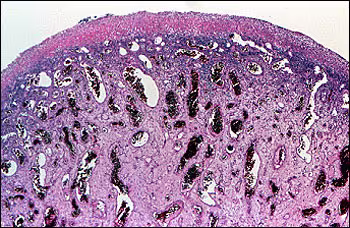

Photomicrographs

Because the large size of the lesion was creating problems with eating and speaking, it was decided to excise the mass and submit it to the Oral Pathology Laboratory. Microscopic examination showed an ulcerated mass of granulation tissue that was covered by a thick fibrinopurulent membrane. (Figure 3)

Figure 3. Low-power photomicrograph showing a mass of highly vascular granulation tissue. The epithelial surface is ulcerated and replaced by a fibrinopurulent membrane.

This tissue was characterized by numerous capillaries which were engorged with red blood cells. (Figure 4)

Figure 4. Medium-power photomicrograph showing dilated blood vessels engorged with red blood cells.